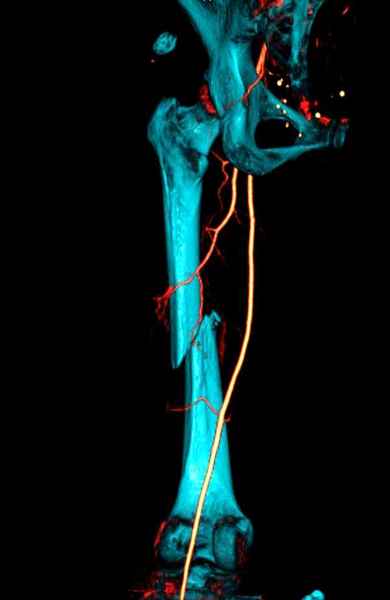

Со слов, больная ничем не болела, только последние 3 месяцев чувствовала боли в бедренной области. КТ брюшной полости подтвердил увеличенную правую почку. (5-6)

Для предупреждения кровотечения во время рассверливания, за день до операции провели эмболизацию сосудов питающий метастаз. http://radiology.rsnajnls.org/cgi/reprint/150/3/673.pdf (7-11, 12-15-16)

С минимальным рассверливанием и ретроградным методом провели остеосинтез бедра 12 мм гвоздем. (17-20)